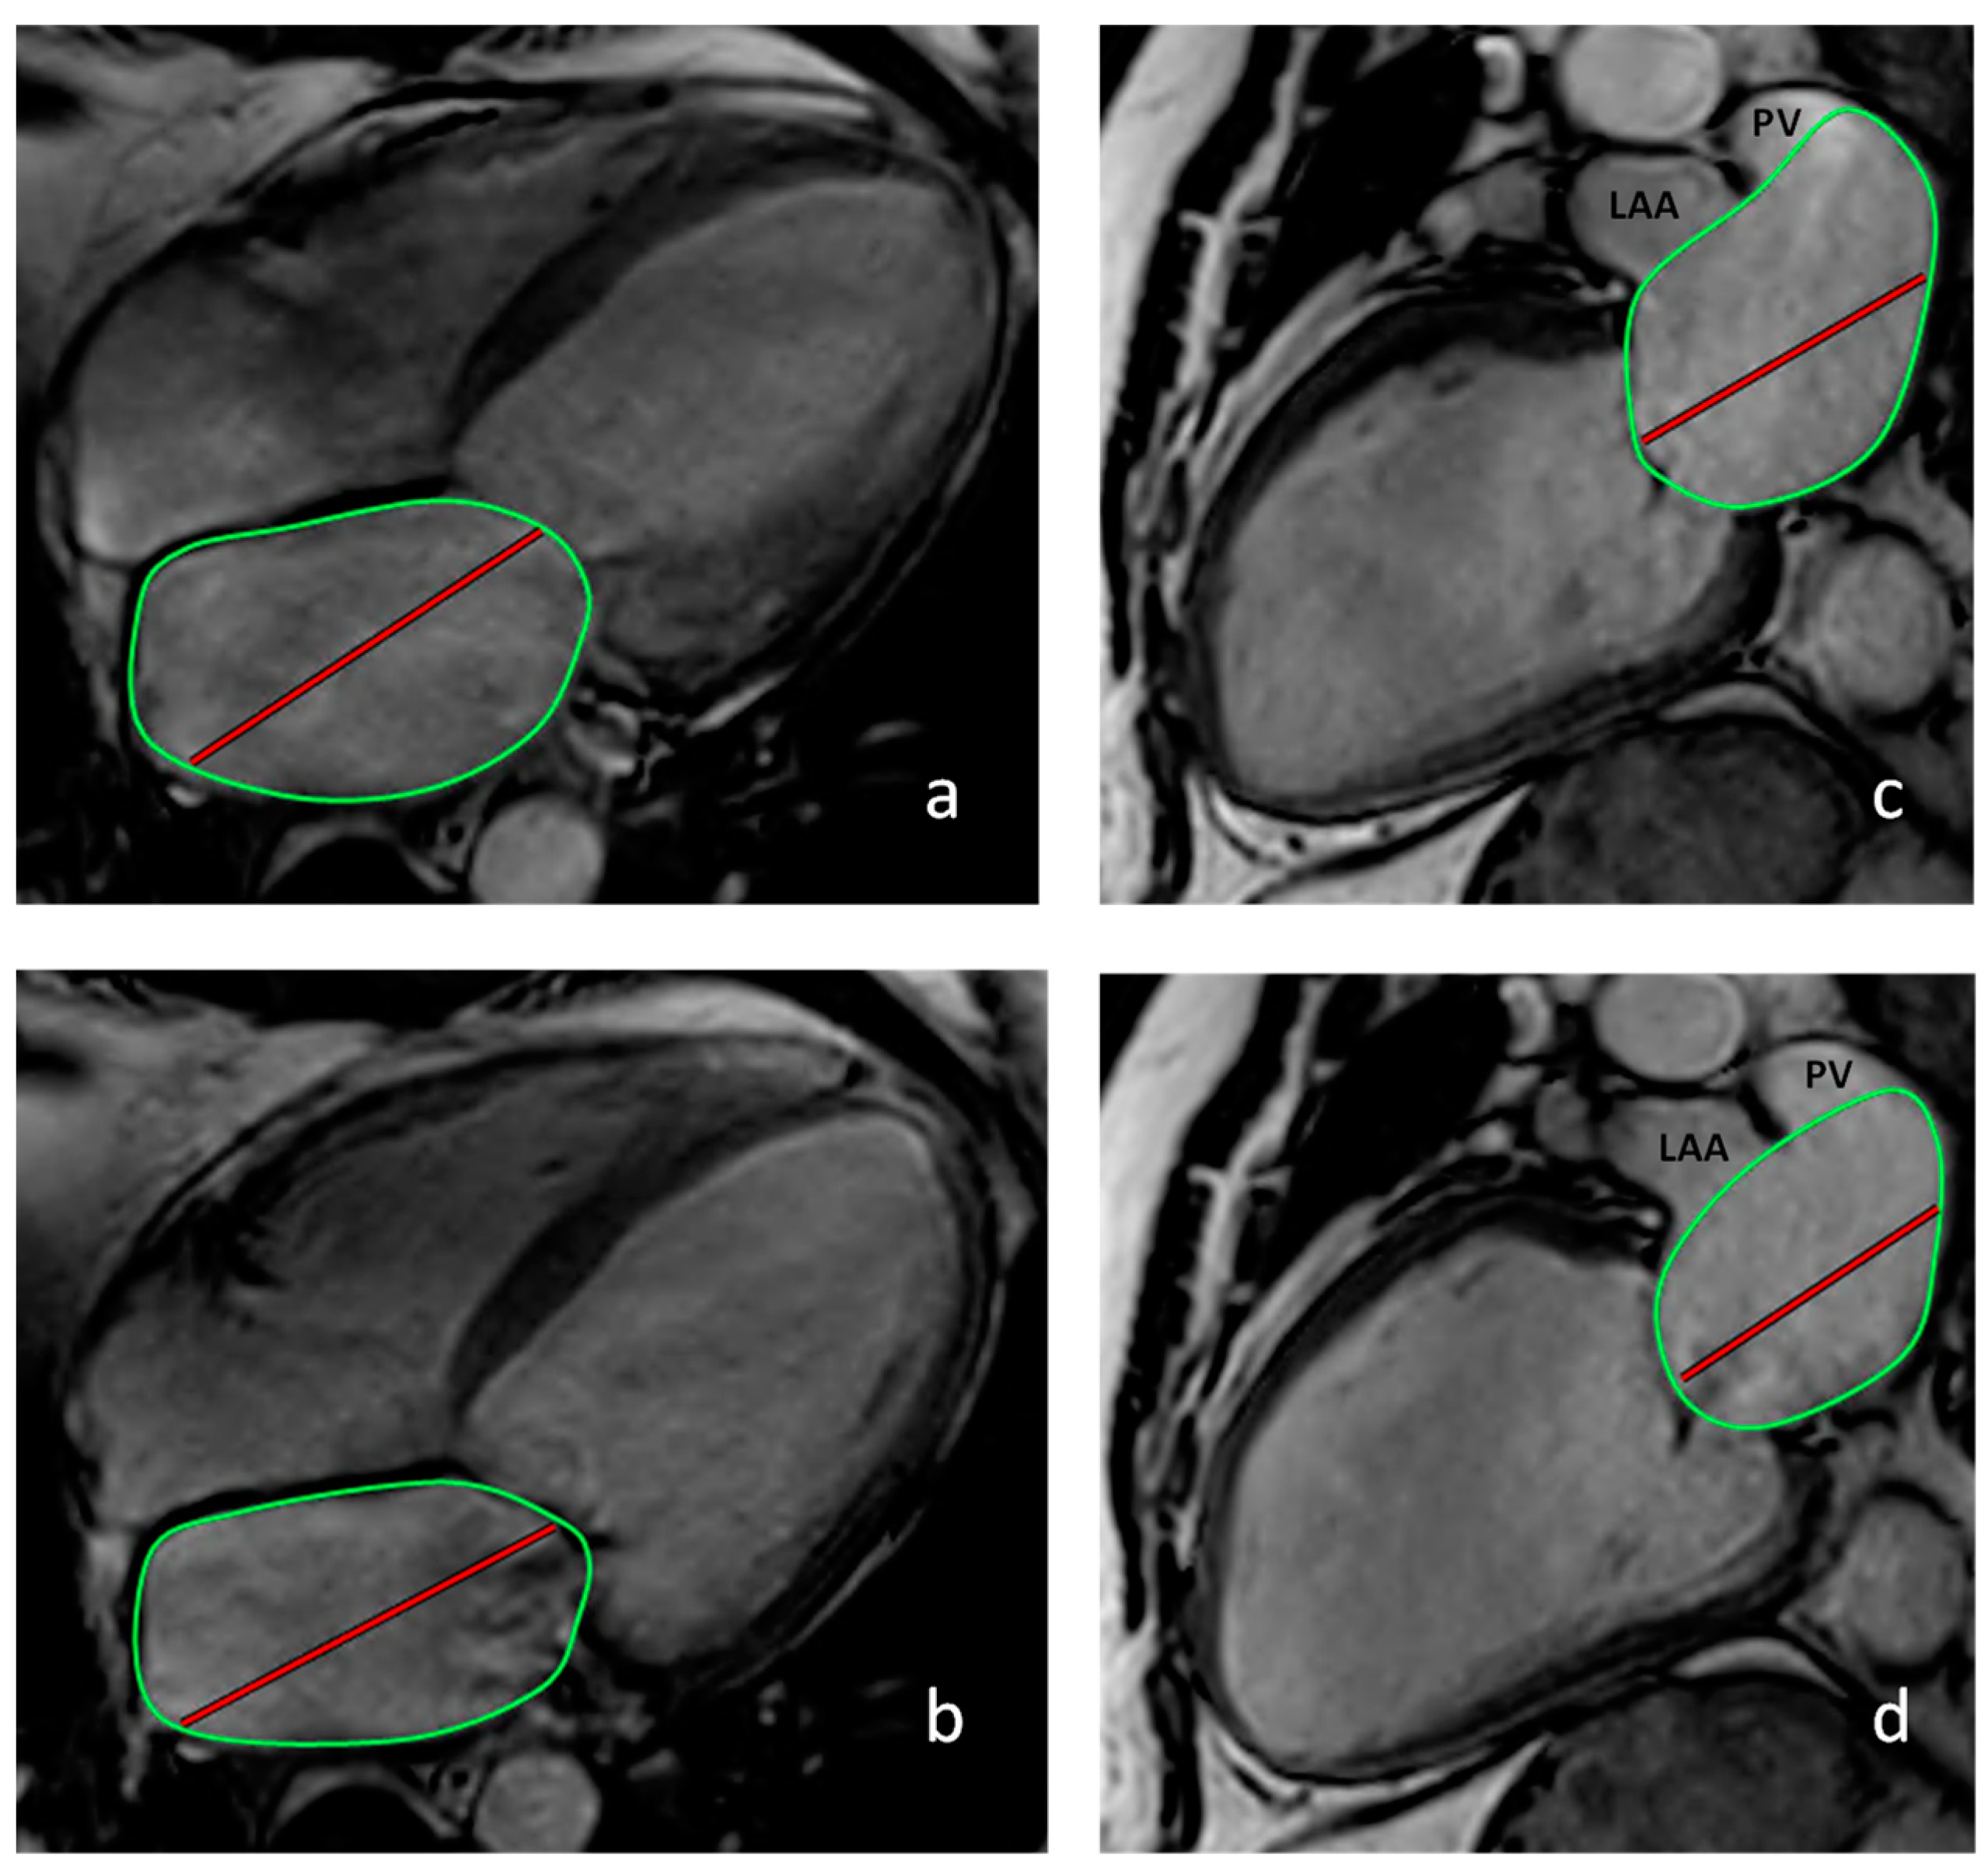

2. Materials and Methods

3.1.2. Cardiac Magnetic Resonance Imaging